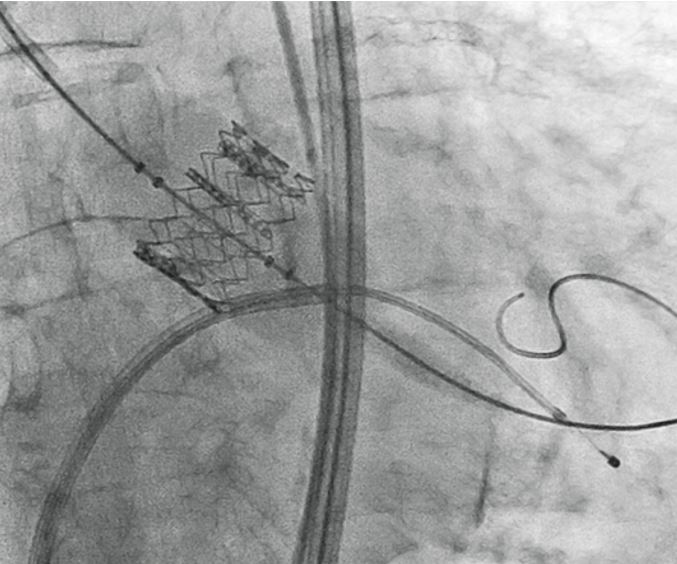

Флюороскопія під час TAVR